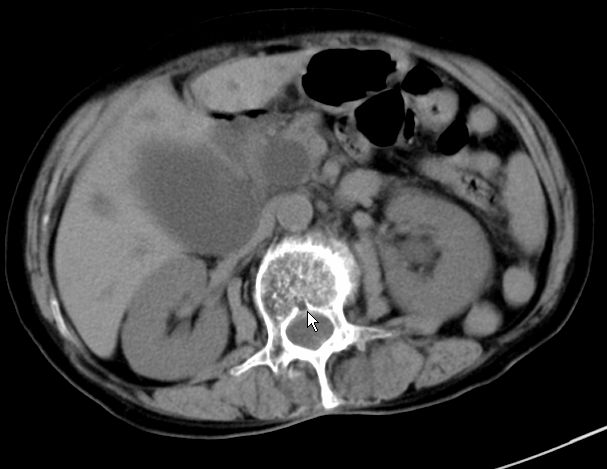

以下是引用zjzjr在2008-12-16 12:49:00的发言:[br]肝内外胆管全程扩张,胆囊明显增大,未见占位征像.建议mrcp.

以下是引用jiangjing在2008-12-16 13:19:00的发言:[br]肝内外胆管全程扩张,胆囊明显增大,扩张胆总管下段径较中上段小,未见胰管扩张,提示胆总管远端梗阻伴感染.建议增强及mrcp 检查

以下是引用朱亮在2008-12-16 12:54:00的发言:[br]胆总管远端应薄层扫描 胆总管逐渐变细 考虑胆系慢性炎症